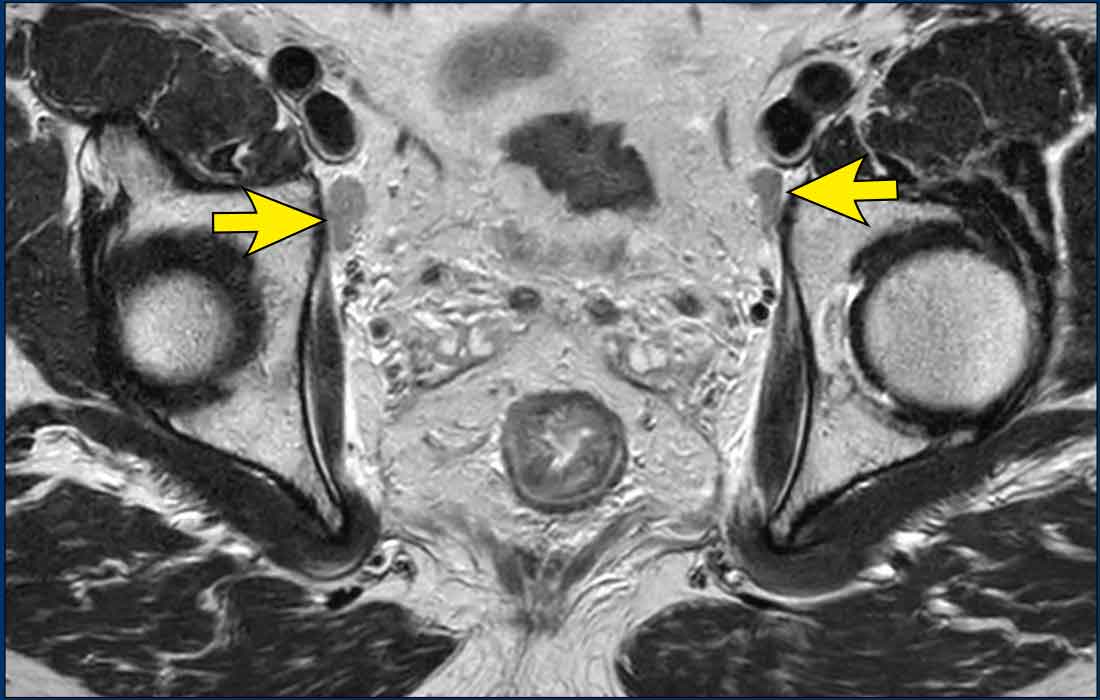

Pitfall – benign nodes dorsal from the external iliac veins

Nodal metastases along the external iliac vessels are rare in rectal cancer and, if present, indicate metastatic disease (cM).

However prominent benign lymph nodes located immediately dorsal to the external iliac veins are a common finding and should not be mistaken for metastases.

These nodes typically have an oval or elongated shape and frequently occur bilaterally (figure).

Their morphology is characteristic of benign reactive lymph nodes, and in most cases, they can be safely omitted from the report.

The 7-mm short-axis cutoff used for assessing obturator and internal iliac nodes is not applicable to external iliac nodes, as reactive nodes in this region frequently exceed 7 mm in short-axis diameter.